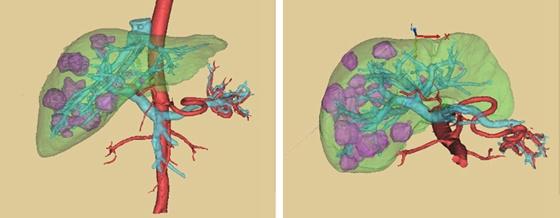

原发性肝癌也是肝脏结节的一种,原发性肝癌指的是肿瘤由肝脏里的细胞发生恶变产生的。包括原发性肝细胞癌,胆管细胞癌,以及混合细胞癌。我国是肝炎大国,大部分肝癌都是继发于肝炎,肝硬化。近年来,酗酒的人群增多,继发于酒精性肝硬化的患者也不少。长期饮酒,有慢性乙肝、丙肝、脂肪肝的患者,一定要定期查肝脏彩超,抽血化验甲胎蛋白AFP。早期的肝癌以手术和射频治疗为主,晚期肝癌以介入治疗,靶向治疗为主。

肝转移癌是指其他地方的肿瘤,转移到肝脏,例如乳腺癌,结直肠癌,肺癌都可以转移到肝脏。因为肝脏的血流非常丰富,肿瘤细胞可以通过血流转移到肝脏。如果出现了肝脏转移,一般就属于肿瘤晚期了,以化疗和靶向治疗为主。

绝大部分人都是体检的时候发现肝脏结节的,如果彩超考虑结节是良性的,例如肝囊肿、血管瘤,那就可以定期的随访,每半年或者一年,复查一个彩超。如果彩超考虑是恶性的或者真的不明确,那就需要做CT或者核磁共振,有助于鉴别诊断,有时候甚至要做肝脏穿刺来明确诊断。